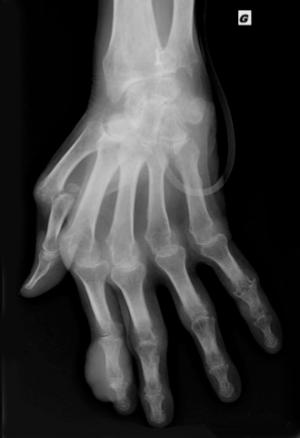

Radiographie de main/poignet gauches de face. Goutte chronique tophacée. Association de lésion destructrices (géodes et érosions) et constructrices : styloïde ulnaire, métacarpophalangiennes (1re et 2e), interphalangiennes proximales (3e, 4e et 5e), interphalangiennes distales (2e et 5e). Pincement des interlignes radio-carpien, radio-ulnaire inférieur, intra-carpiens et des métacarpo- phalangiennes (2e, 3e, 4e, 5e). Luxation de la 1re métacarpophalangienne. Volumineux tophus en regard des interphalangiennes proximale et distale du 2e doigt.